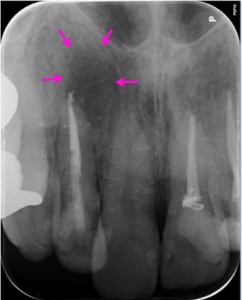

治療後1年

根の治療1年後のレントゲン写真です。矢印の骨の溶けていた部分は周囲との境界がなくなり、溶けている部分がわからなくなりました。歯の根の周りに一層の骨との境界のライン(歯と骨をつなぐ歯根膜という組織がある部分です)が回復し、歯の周囲組織の本来の姿を取り戻し、完全な回復が見られます。

治療前後

上の2番目の歯は根の先が曲がっており、従来の歯の根の治療では先の部分がうまく清掃、殺菌できず、再治療が多い歯でもあります。しかし、歯の根に合わせて柔軟に曲がって根の中のばい菌をしっかり除去できるニッケルチタンファイルを使用し、抗菌性のある材料で根の中をつめると、炎症で骨が溶けている部分が大きいこのような歯でも治癒に導くことができます。